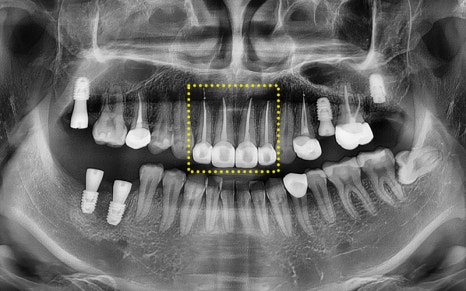

실제로 진료기록에서도 확인되듯이

10개가 넘는 치아에 대해

신경치료(근관치료)를 받으셨고,

대부분 복잡한 염증과 신경 감염이

동반되어 있었습니다.

특히 윗니 앞니와 어금니까지

넓은 범위에 걸쳐

치료가 진행되었습니다.

파노라마 사진을 촬영해

정밀 체크를 진행하였고,

전체적인 치료를 계획하였습니다.

파노라마상에서도 성공적으로

치료가 진행 된 모습을 체크하실 수 있습니다.

현재 임플란트는

인공치근 부분인

픽스처만 식립되어 있는 상태로,

추후 크라운(보철물)을 올리는

보철과정까지 잘 마무리 해드리기로 했습니다.